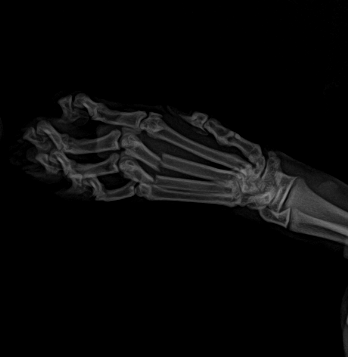

落下の衝撃で指の骨が折れていたため肺の状態の回復を待って骨折の手術も行いました。この症例は翌日退院しております。